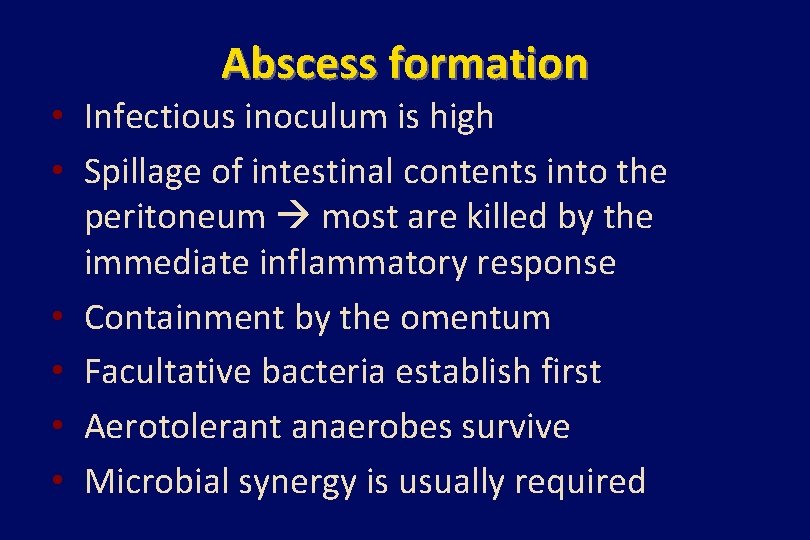

Abscess formation • Infectious inoculum is high • Spillage of intestinal contents into the peritoneum most are killed by the immediate inflammatory response • Containment by the omentum • Facultative bacteria establish first • Aerotolerant anaerobes survive • Microbial synergy is usually required